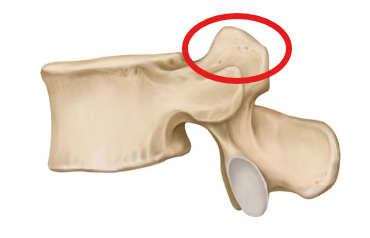

Lumbar vertebra

Superior articular process

Transverse process

Inferior articular facet

Superior articular facet

Lamina

Pedicle

Vertebral foramen